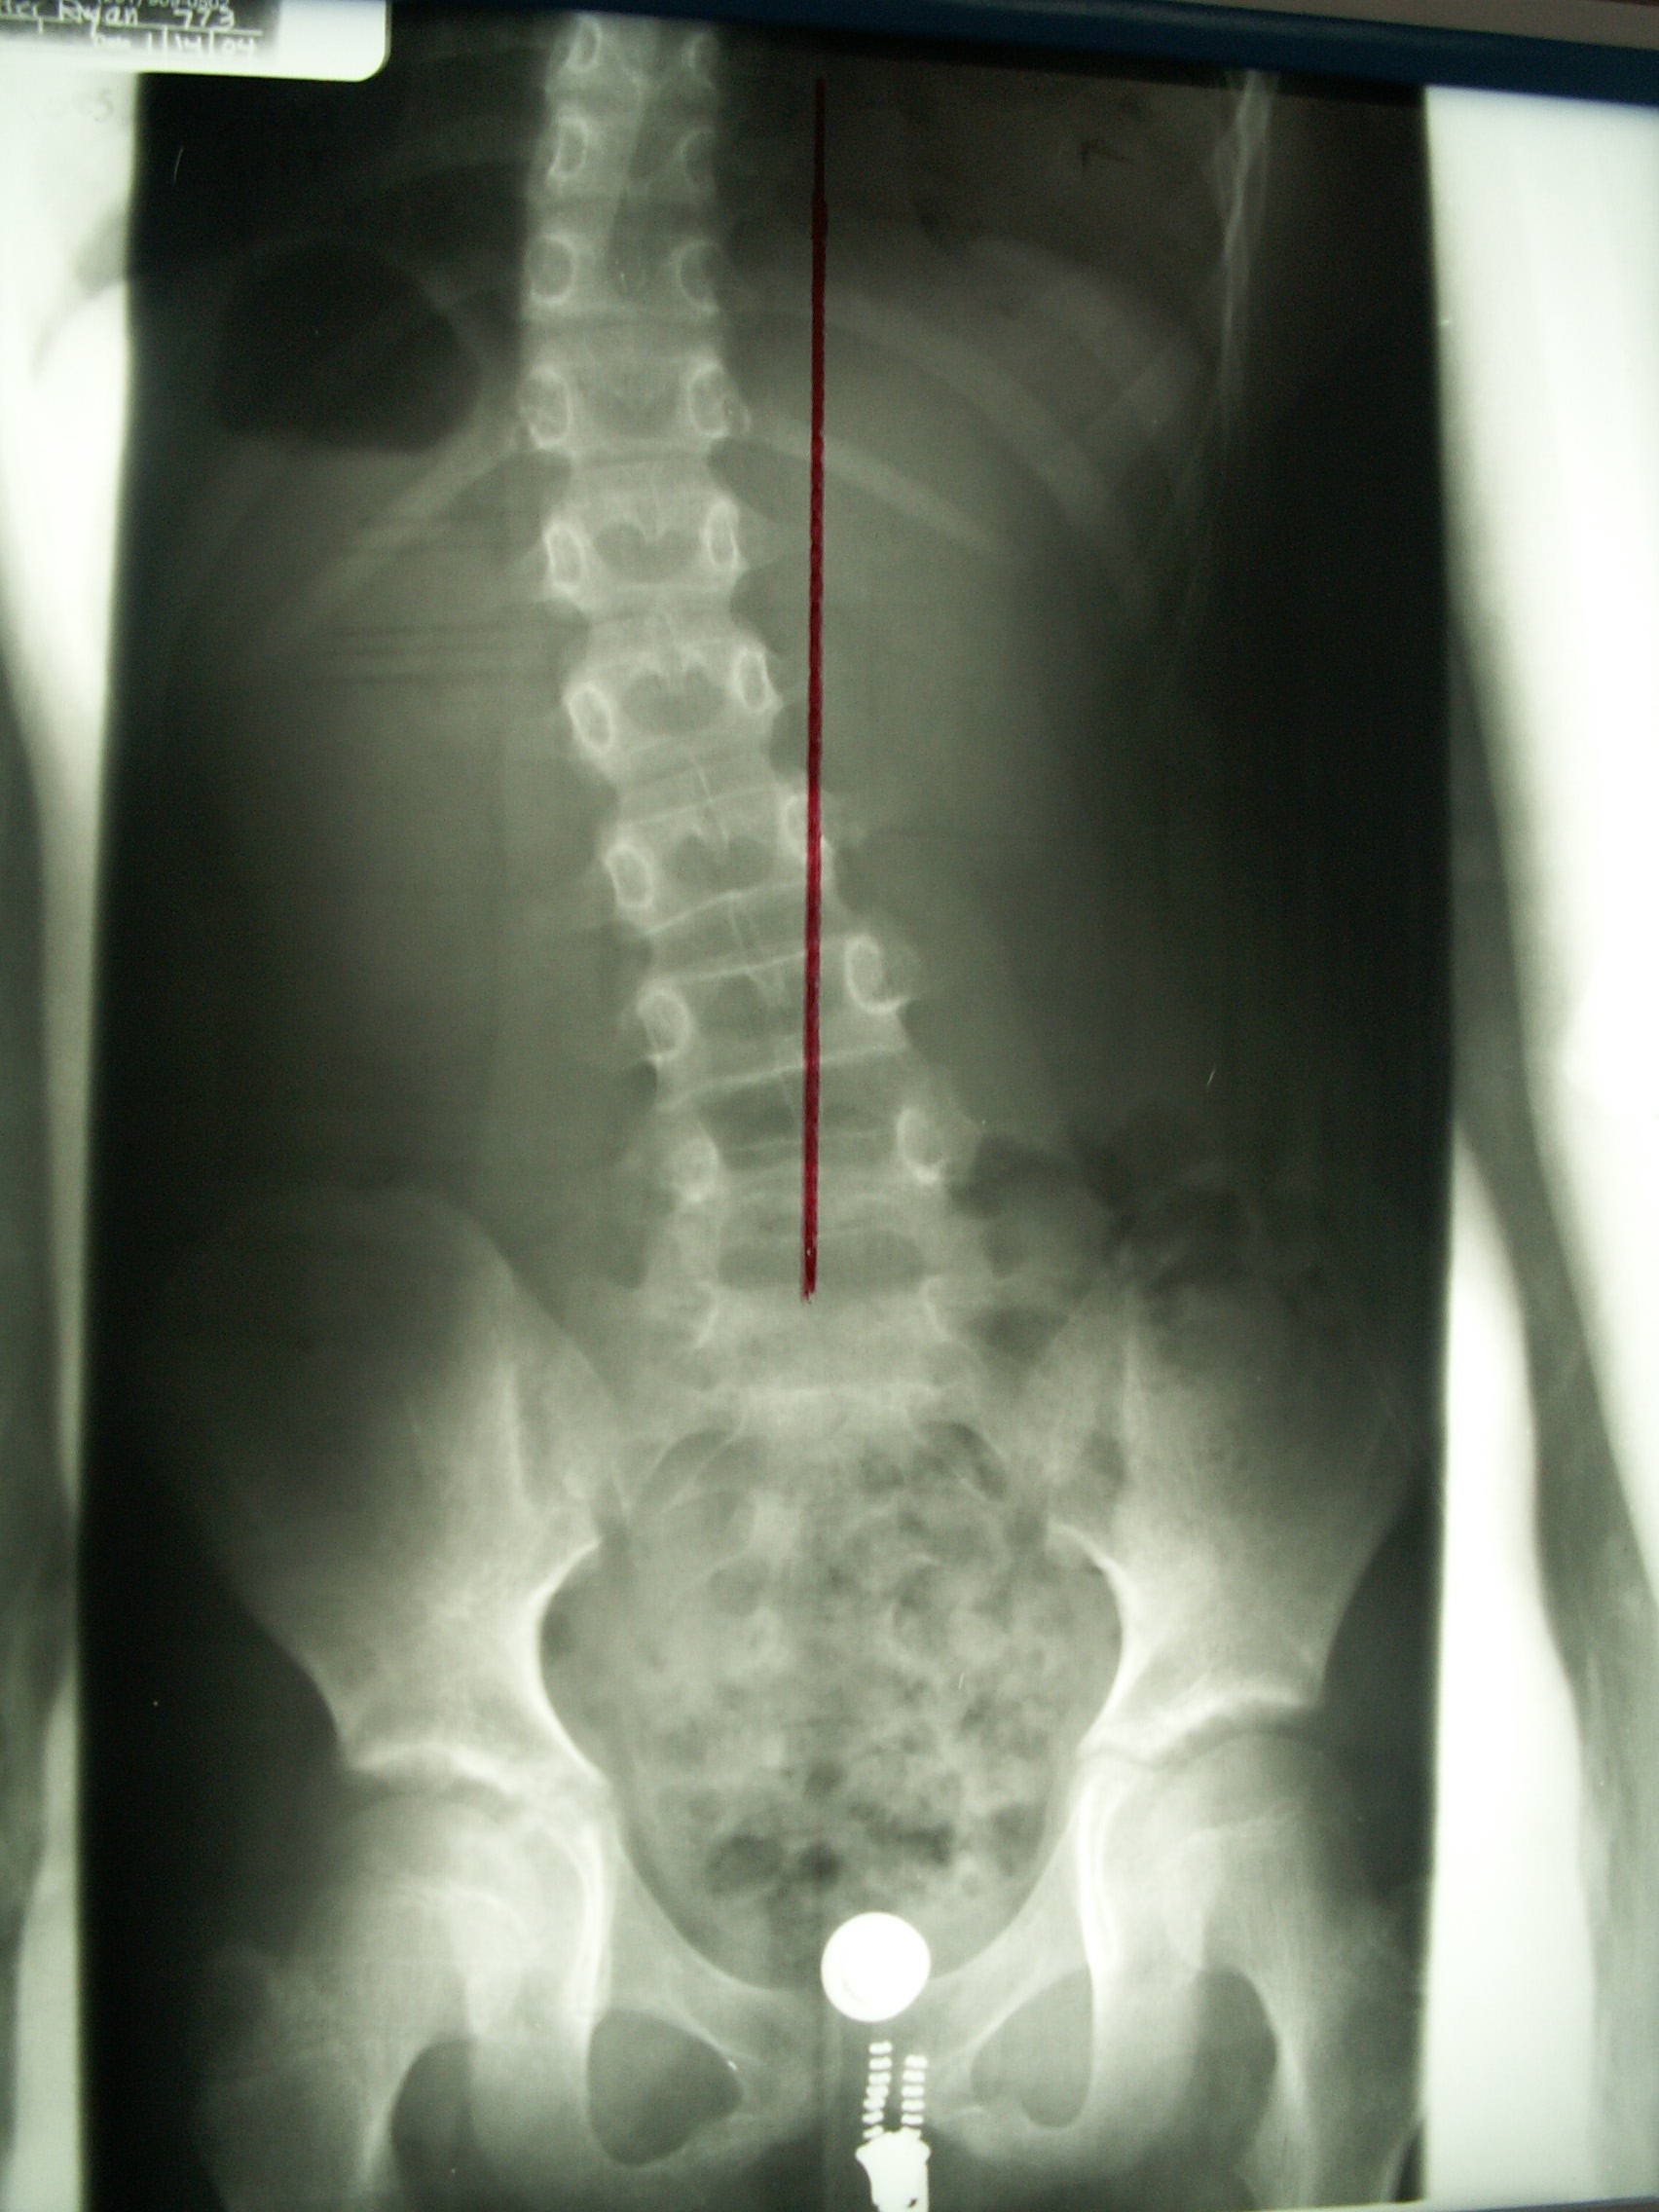

X-rays (radiographs) – X-rays include an upright front-to-back view of the spine.

Cobb Angle Measurement – This test uses an x-ray to calculate the angle of the curve(s).

Risser Sign – An x-ray to provide information about skeletal maturation. The Risser Sign looks at the iliac crest growth plate, a fan-shaped part of the pelvis. The crest fuses with the pelvis at maturity.